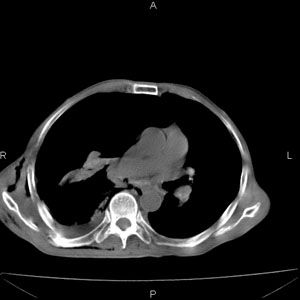

患者男,77岁,于3日前从树上摔下,头部查ct示蛛血,硬膜下出血,上腹部ct未见明显异常,右侧胸腔积液,左侧如常。肺部拍片示右侧肋骨多发骨折住院后今日来查肺部ct,我看到的是1。右侧胸腔血气胸并右肺上叶,中叶压缩性肺不张,2。右肺下叶肺挫伤并多发肋骨骨折,肌内及皮下积气3。左侧少量胸腔积液,我想请教的是3天前左侧胸腔里没有积液今天怎么出现了呢,是什么原因呢?请讨论。

有肺挫裂伤,有渗出,

回复楼主   左侧液气胸,液体来源1、肯定有血液成分,多少不一定。2、胸膜腔渗液,由于肺压缩、活动度下降,肯定胸膜吸收有问题,导致积液增多。

因为3天前病人刚摔的时候,左侧胸腔受伤不严重,故而当时没有胸腔积液,但病人受到这么大的伤害,胸膜腔内的液体动态平衡肯定会受到影响,所以过一段时间后才出现胸腔积液。

1、外伤出血需要一定的时间

2、气胸存在时间长了,产生的胸膜渗液

考虑外伤性迟发性胸腔积液。

右侧液气胸,胸膜创伤、肺组织挫伤,渗出属正常反应。